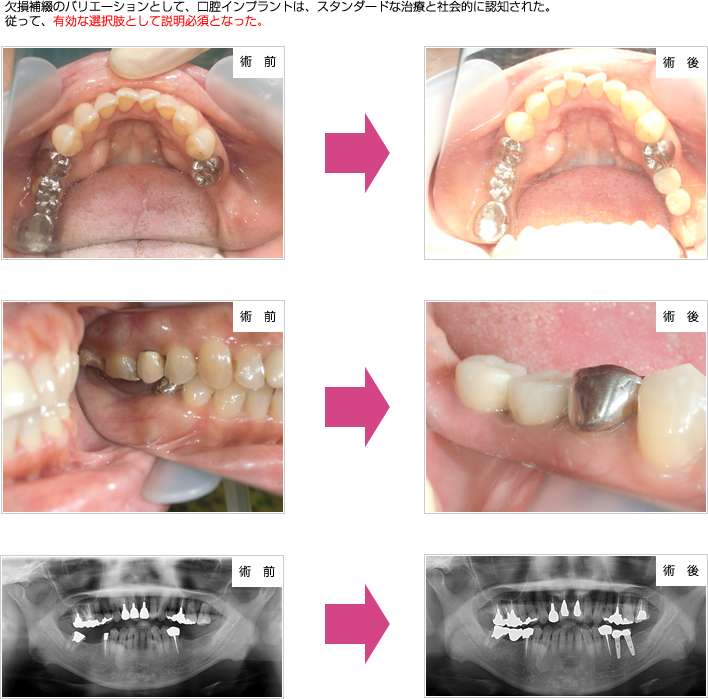

歯科インプラント治療は、歯を失った場合にそれを補う治療のひとつです。

歯を失った場合の治療の選択肢には、その他入れ歯やブリッジがあり、 この歯科インプラント治療を含めた3つの治療方法から医学的・日常生活的また経済的事情を 考慮した医療面接を行い決定していきます。